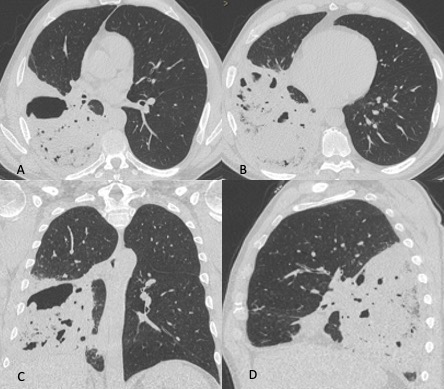

Figura 1: Uomo di 75 anni con infezione da SARS-CoV-2. Le immagini TC assiali (A-B-C-D) e ricostruzioni MPR sul piano sagittale (E) e coronale (F) mostrano la tipica presentazione della polmonite da COVID-19 caratterizzata dalla presenza di aree di aumentata densità con aspetto a “vetro smerigliato” cui si associa ispessimento liscio dei setti interlobulari che mostrano prevalente distribuzione subpleurica. La localizzazione delle aree di iperdensità in sede subpleurica è caratteristica di questa infezione come evidenziato particolarmente nell’immagine A in cui le aree a “vetro smerigliato” si dispongono lungo la scissura del lobo accessorio dell’azygos e nell’immagine E in cui è evidente la distribuzione delle alterazioni lungo le scissure.

Figura 3: Uomo di 65 immunocompromesso affetto da polmonite da Citomegalovirus. Le immagini TCAR assiali (A-B-C) e la ricostruzione MPR coronale (D) mostrano il tipico pattern caratterizzato dalle presenza di "vetro smerigliato" diffuso in entrambi i polmoni con distribuzione simmetrica, si associa la presenza di alcune aree di aumentata densità con aspetto consolidativo in entrambi i lobi inferiori.

Figura 4: Donna di 78 anni con diagnosi di Linfoma di Hodgkin. Le immagini assiali (A-B-C) mostrano il parenchima polmonare normale. Un anno dopo la paziente giunge al Pronto Soccorso per un rapido peggioramento della funzionalità respiratoria, dispnea e tosse. La TCAR eseguita alcuni giorni dopo il ricovero nel reparto di Malattie Infettive (D-E-F) mostra la presenza in entrambi i polmoni di "vetro smerigliato" diffuso con relativo risparmio delle zone sub-pleuriche e la comparsa di formazioni pseudocistiche nel lobo superiore sinistro (frecce in D ed E). L’ipotesi formulata e poi confermata dal laboratorio è stata quella di polmonite da Pneumocystis Jirovecii.

Figura 5: Uomo di 68 anni immunocompromesso giunge al Pronto Soccorso per IRA. La TCAR eseguita all’ingresso (immagini assiali A-B-C e la ricostruzione MPR sul piano coronale D) mostrano "vetro smerigliato" diffuso e simmetrico in entrambi i polmoni con relativo risparmio delle aree sub-pleuriche solo in alcune zone nel polmone. L’ipotesi diagnostica formulata è stata quella di polmonite interstiziale. Le indagini di laboratorio hanno in seguito rivelato che l’agente patogeno responsabile del quadro flogistico era lo Pneumocystis Jirovecii. La diagnosi differenziale tra le varie cause di iperdensità parenchimale nei pazienti con IRA non è semplice soprattutto quando le alterazioni sono molto estese e diffuse.